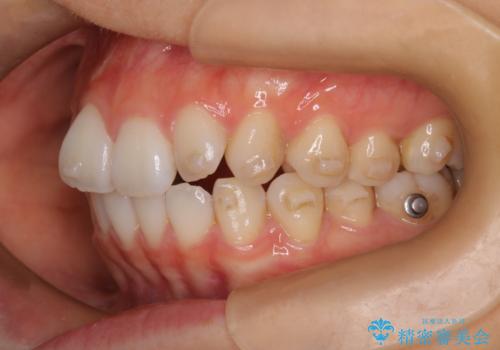

- 前歯の凸凹を主訴に来院されました。

スペースを作るために顎間ゴムを使用して、奥歯の遠心移動をおこない配列しました。

奥歯の遠心移動を行うことで、犬歯関係も良い状態に仕上げることができました。